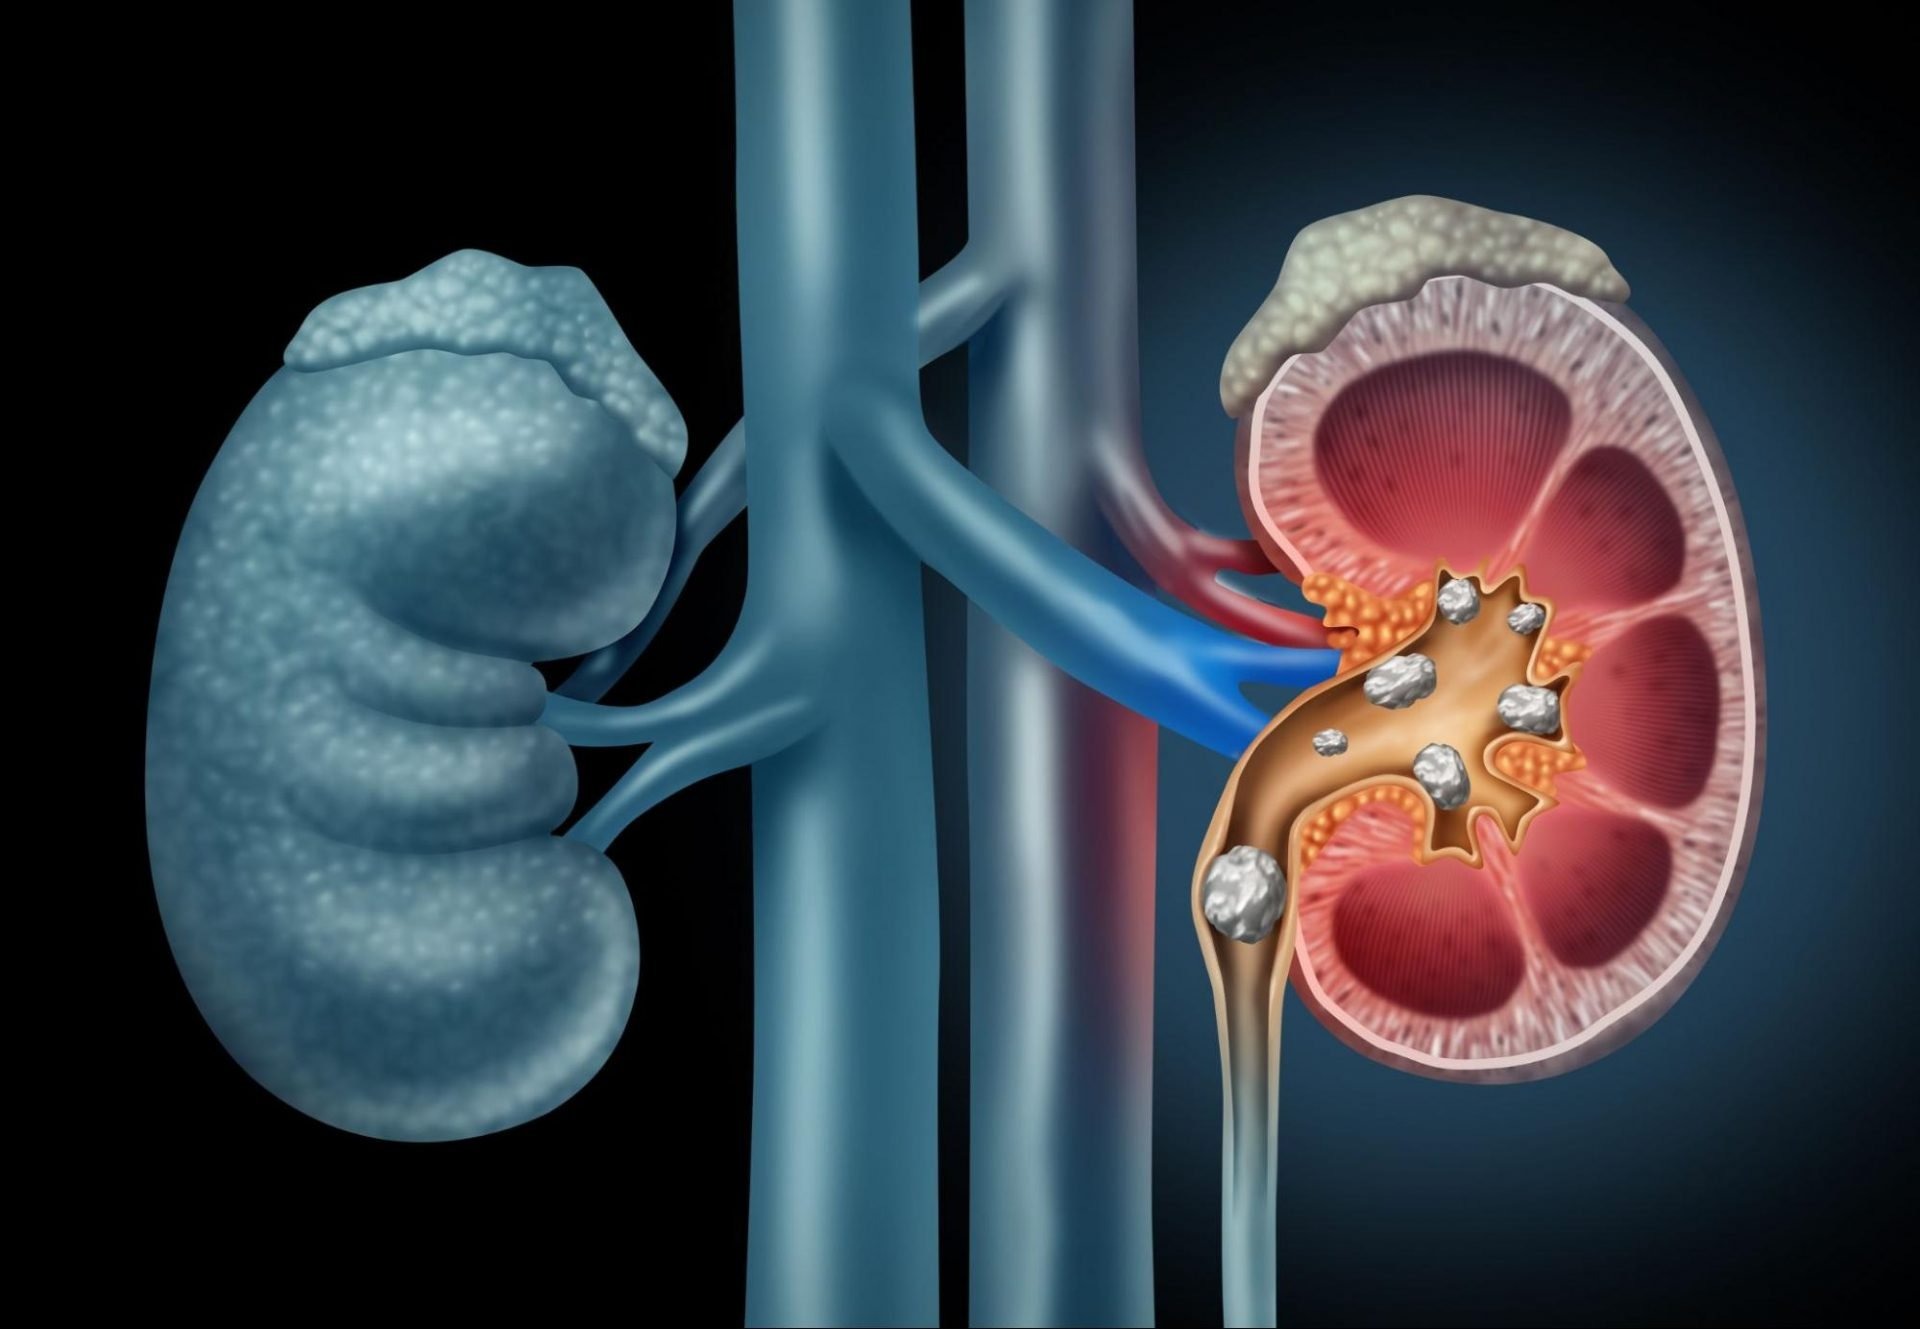

જો તમારા વિસ્તારમાં ગંદુ પાણી પૂરું પાડવામાં આવી રહ્યું હોય તો તે સ્વાસ્થ્ય માટે હાનિકારક હોઈ શકે છે. દૂષિત પાણી પીવાથી અનેક રોગોનું જોખમ વધે છે. દૂષિત પાણી પેટમાં ચેપ, ટાઇફોઇડ, કોલેરા અને હેપેટાઇટિસ જેવા રોગોનું કારણ બની શકે છે. એટલું જ નહીં, દૂષિત પાણી કિડનીમાં પથરીનું કારણ પણ બની શકે છે. તાજેતરના એક સંશોધનમાં જાણવા મળ્યું છે કે ખરાબ પાણી પીવાથી કિડનીમાં પથરી થવાનું જોખમ અનેક ગણું વધી જાય છે. એટલું જ નહીં, વારંવાર ગંદુ પાણી પીવાથી કિડનીમાં પથરી થઈ શકે છે.

અમેરિકન યુરોલોજિકલ એસોસિએશનની વાર્ષિક બેઠકમાં કરવામાં આવેલા એક સંશોધનમાં આ વાત પ્રકાશમાં આવી છે. આ સંશોધનમાં, લગભગ 1142 લોકો પર સંશોધન કરવામાં આવ્યું હતું જેમાં 90 લોકોમાં પથરીનું કદ અન્ય લોકો કરતા ઘણું મોટું જોવા મળ્યું. આ બધા 90 લોકો ખૂબ પ્રદૂષિત સ્થળોએ રહે છે. આ લોકોમાં ફરીથી પથરી થવાનું જોખમ પણ અન્ય લોકો કરતા વધારે જોવા મળ્યું.

પ્રદૂષિત પાણી પીવાથી કિડનીમાં પથરી થઈ શકે છે

સંશોધનમાં સમાવિષ્ટ લોકોમાંથી, 46.6 ટકા લોકોને ફરીથી કિડનીમાં પથરી થવાનું જોખમ જોવા મળ્યું. ૪૧.૧ ટકા લોકોને બહુવિધ પથરી થવાનું જોખમ જોવા મળ્યું. ખરાબ પાણીને કારણે થતી પથરીનું કદ પણ મોટું હોઈ શકે છે. પથ્થરનું કદ 21 મિલીમીટર સુધીનું હોઈ શકે છે.

કિડનીમાં પથરી થવાના કારણો

જોકે, અત્યાર સુધી કિડનીમાં પથરી થવાના મુખ્ય કારણો ખરાબ ખોરાક અને ઓછું પાણી પીવું માનવામાં આવતું હતું. આ ઉપરાંત, આબોહવા સંબંધિત કારણો પણ જવાબદાર માનવામાં આવે છે. આ ઉપરાંત શરીરમાં પાણીની ઉણપથી પણ પથરી થવાનું જોખમ વધે છે. વધુ પડતું મીઠું ખાવાથી પથરી થઈ શકે છે. શરીરમાં પ્રોટીન, કેલ્શિયમ અને સોડિયમ વધવાથી પણ પથરી થવાની શક્યતા વધી જાય છે. છેલ્લા કેટલાક વર્ષોમાં ભારતમાં પથરીની સમસ્યા ઝડપથી વધી રહી છે. જેમાં શહેરોમાં રહેતા લોકોની સંખ્યા વધુ જોવા મળે છે.